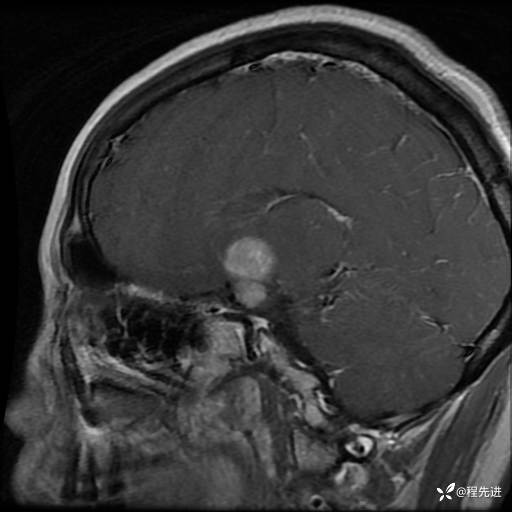

MRI平扫+增强:

T1:

T2: